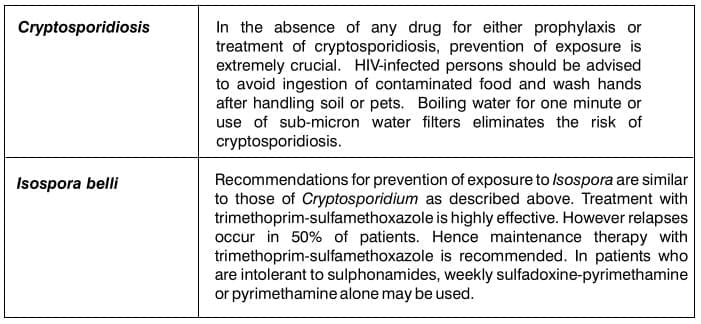

- Bacteria: Salmonella, Shigella, Campylobacter

- Parasitic infections: Cryptosporidium, Isospora, Giardia, Microsporidia, Entamoeba histolytica

Parasitic infections

Cryptosporidium, Isospora, Giardia and Microsporidia all infect the small intestine.

Entamoeba histolytica is uncommon but when present involves the caecum, ascending colon and terminal

ileum. Strongyloides stercoralis may also be encountered. The diagnosis can be established through

microscopic identification of oocytes in stool or tissue.